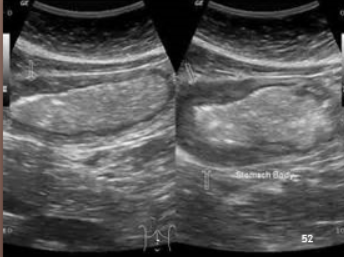

Regular stomach